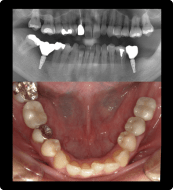

一番奥の入れ歯が噛みにくい方

BEFORE

AFTER

症例概要

年代・性別

50歳代 女性

主訴

奥歯で噛めない

治療内容

右下6番インプラント治療

治療期間

3ヶ月

治療のリスク

骨の状態によっては骨造成が追加で必要な場合があります。

メンテナンスやセルフケアの状態でインプラントの歯周病に犯される場合があります

治療費用

407,000円(税込)